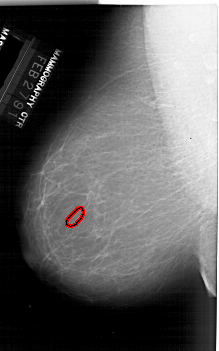

A_1916_1.LEFT_CC

LEFT_CC LINES 6406 PIXELS_PER_LINE 3886 BITS_PER_PIXEL 12 RESOLUTION 43.5 OVERLAY

FILE: A_1916_1.LEFT_CC.OVERLAY

TOTAL_ABNORMALITIES 1

ABNORMALITY 1

LESION_TYPE CALCIFICATION TYPE PUNCTATE DISTRIBUTION CLUSTERED

ASSESSMENT 4

SUBTLETY 1

PATHOLOGY BENIGN

TOTAL_OUTLINES 1

BOUNDARY